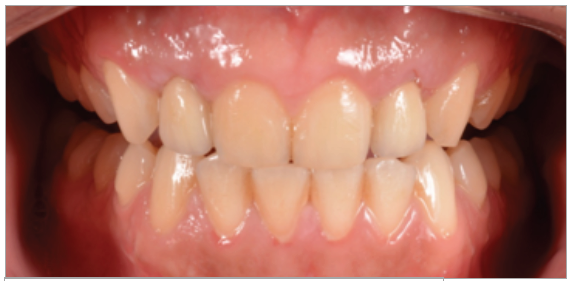

Paciente de sexo masculino de 24 años de edad, de raza mestiza, sin antecedentes sistémicos y oclusalmente estable, que fue transferido al servicio de Rehabilitación Oral del Posgrado y Especialización de la Universidad Peruana Cayetano Heredia, Lima, Perú. Recibió previamente tratamiento ortodóncico en el servicio de Ortodoncia y Ortopedia Maxilar por 6 años. Al examen intraoral presentó agenesia de las piezas 12 y 22 con evidencia de defectos óseos, presenta fenotipo periodontal grueso (figura 1). Al examen radiográfico se observa disminución generalizada de las raíces (Rizomicri), presenta ensanchamiento del ligamento periodontal generalizado (figura 2). Para el plan de trabajo para el diagnóstico se obtuvieron modelos de estudio primario, realizando el encerado para la planificación del tratamiento del sector anterosuperior. Al análisis tomográfico se evidenció poca disponibilidad ósea, motivo por el cual se planificó dos injertos en bloque de mentón con hueso particulado y plasma rico en plaquetas previo a la colocación de implantes dentales (figura 3 y figura 4). Pasado el tiempo de osteointegración (6 meses) se colocaron dos implantes Strong WS Cono Morse (SIN®, Sao Paulo, Brasil) de 3.5 mm x 11 mm. En la segunda fase, se confeccionaron provisionales de acrilico termocurado Vitalloy® (Vitacryl; A. Tarrillo Barba S.A., Lima, Perú) para el manejo de los tejidos blandos a nivel de las piezas 12 y 22, los cuales estuvieron fijados a un cilindro provisional de titanio (SIN®, Sao Paulo, Brasil) atornillado al implante, verificando la adaptación de este al implante mediante una radiografía periapical (figura 5). El cilindro fue recortado dando una altura de 6 mm, los provisionales fueron agujerados en el medio (figura 6), de tal forma que el cilindro calce en el medio del espacio edéntulo, se cubrió la entrada del cilindro con teflón (Golfo USA®) y se capturó el cilindro con acrílico de autocurado Duralay color 62 (Reliance Dental Manufacturing LLC, Illinois USA) (figura 7). Después del acrilizado se retiró el provisional, en la parte cervical se realizó un incrementó con resina fluida (Filtek™ Z350XT Flow - 3M ESPE Dental Products. St. Paul, Minnesota, USA) formando el contorno crítico a 2mm por debajo del zenit de los incisivos centrales de tal manera que entre los zenits de los incisivos centrales, laterales y caninos formen una zona triangular. El contorno subcrítico se realizó de forma convexa (figura 7 y figura 8). Se finalizó con el acabado y pulido del provisional con gomas de grano grueso (gris) y grano fino (verde) (Politip, Ivoclar-Vivadent; Schaan, Liechtenstein). Se manejó la conformación de los tejidos blandos en 2 citas mediante la adición por capas de resina compuesta (Filtek™ Z350 - 3M ESPE Dental Products. St. Paul, Minnesota, USA) a nivel del contorno crítico y subcrítico a las 2 semanas y 4 semanas de la instalación del provisional (figura 9 y figura 10). Se logró conformar las papilas interdentales, el contorno crítico y subcrítico observando que los tejidos se encontraran estables, sin inflamación, con el color de la encía igual a la encía adyacente; todo esto nos indicó que se podía realizar la impresión definitiva. La instalación final se realizó con coronas metal cerámicas cementadas (figura 11 y figura 12).